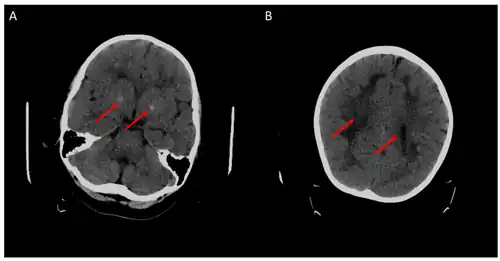

До и после возобновления терапии лейковорином при недостаточности ДГПР

- 1 2 Pappalardo MG, Di Nora A, Giugno A, Meli C, Sapuppo A, Pavone P, Fiumara A (September 2022). Dihydropyridine Reductase Deficiency: Acute Encephalopathy Related to Folinic Acid Treatment Interruption in a Girl. Global Medical Genetics. 9 (3): 247–251. doi:10.1055/s-0042-1756661. PMC 9484871. PMID 36132999.